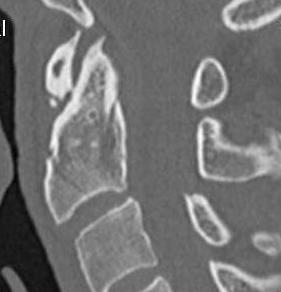

Anatomy

Superior projecting bony element of C2 / axis

C1 / atlas rotates around the dens to provide cervical rotation

Classification Anderson & D'alonzo

Type 2

Fracture of base of odontoid process

- most common type

- > 50%

Type 3

Fracture through body of axis

Type II Dens Fracture